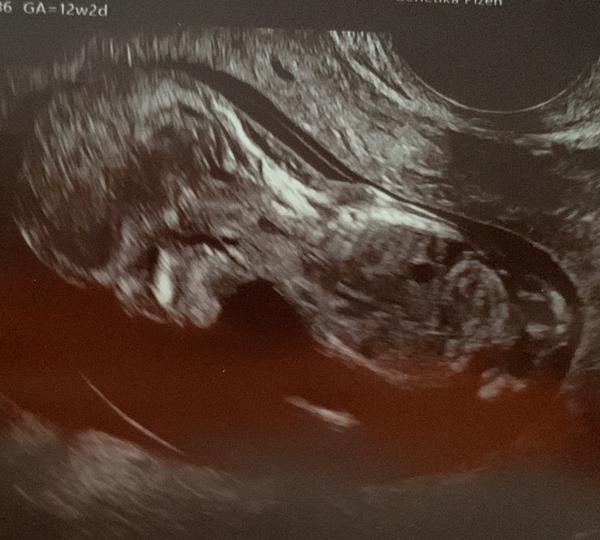

@reeeza tak náš malý měl šíjové projasnění 5,4 a limit je 2,5. Doktor se se mnou bavil v podstatě tak, že je to škoda, protože plod jinak vypadá dobře, ale hned se mnou probíral možnosti případného potratu. Na výsledky jsme čekali 3 týdny, spousta stresu a pláče a je to spokojené, usměvavé miminko. Takže i kdyby tam mělo miminko více tekutiny, nemusí to vůbec nic znamenat. 🙂 Testy jsem si platila neinvazivní a dělali to v Plzni. Tam je na to specializované pracoviště.

@reeeza jinak nase fotky z prvotrim screeningu vypadaly takto..